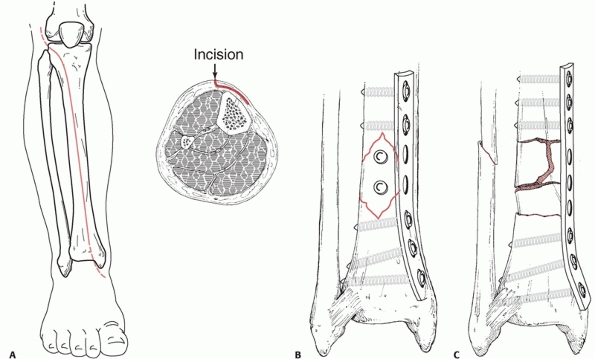

longitudinal. A longitudinal incision is made 1 cm lateral to the crest

of the tibia. The entire anterior aspect of the tibia can be visualized

through this incision as well as the anterolateral or anteromedial

aspects of the tibia. Minimally invasive approaches to the tibia can

also be used. A direct medial approach to the distal tibia just

overlying the medial malleolus will permit medial minimally invasive

plate osteosynthesis of the distal tibia. This incision can be placed

medially, anteromedially or posteromedially, and it may also curve

anteriorly or posteriorly at the distal end of the medial malleolus.

For minimally invasive plate osteosynthesis of the proximal tibia, an

anterolateral approach is used and will be described later in the

chapter. Traditionally, a posterolateral approach to the tibia has been

used for bone grafting when the soft tissues overlying the anterior

aspect of the tibia are not of good quality, due either to the presence

of open wounds or

previous surgical exposures.120

This approach is undertaken along the posterior border of the fibula

and over the posterior aspect of the interosseous septum. The interval

is developed between soleus and flexor hallucis longus and the peroneal

muscles. Tibialis posterior is dissected from its origin on the

interosseous membrane and retracted medially.120 The neurovascular structures are protected by the muscles of the deep posterior compartment during the dissection.